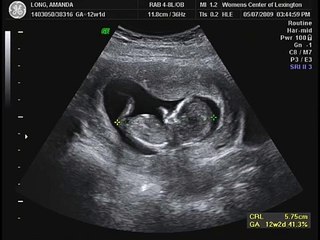

Subscribe for more amazing content. This particular image is for a fetal ultrasound scan for 10-13 weeks gestation. As soon as our Dr found our baby we could.

The Nuchal Translucency was normal 11 mm. This is around the time that the fetus begins to form from the embryo. The baby is measuring 741 cm long 292 in and has a heart rate of 140 bpm.

A vaginal ultrasound will detect the fetus. Baby is measuring at 10 weeks5 days so basically spot on to what we were tracking. I am 10 weeks 4 days today and I had my first ultrasound it was extremely exciting and beautiful.